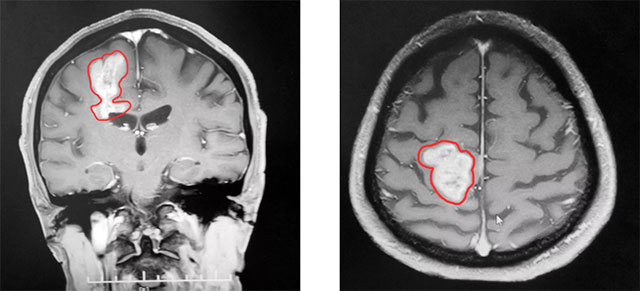

到院时,患者左下肢肌力明显下降,走路不稳。头颅MRI平扫+增强+MRS+MRSI提示:右侧顶叶占位性病变。根据患者影像学检查及检验结果分析,专家认为颅内肿瘤恶性可能性大,并肿瘤性质不明,造成患者生活质量下降,应尽快行手术治疗,明确病理诊断。

▲ MR显示肿瘤近4厘米大小